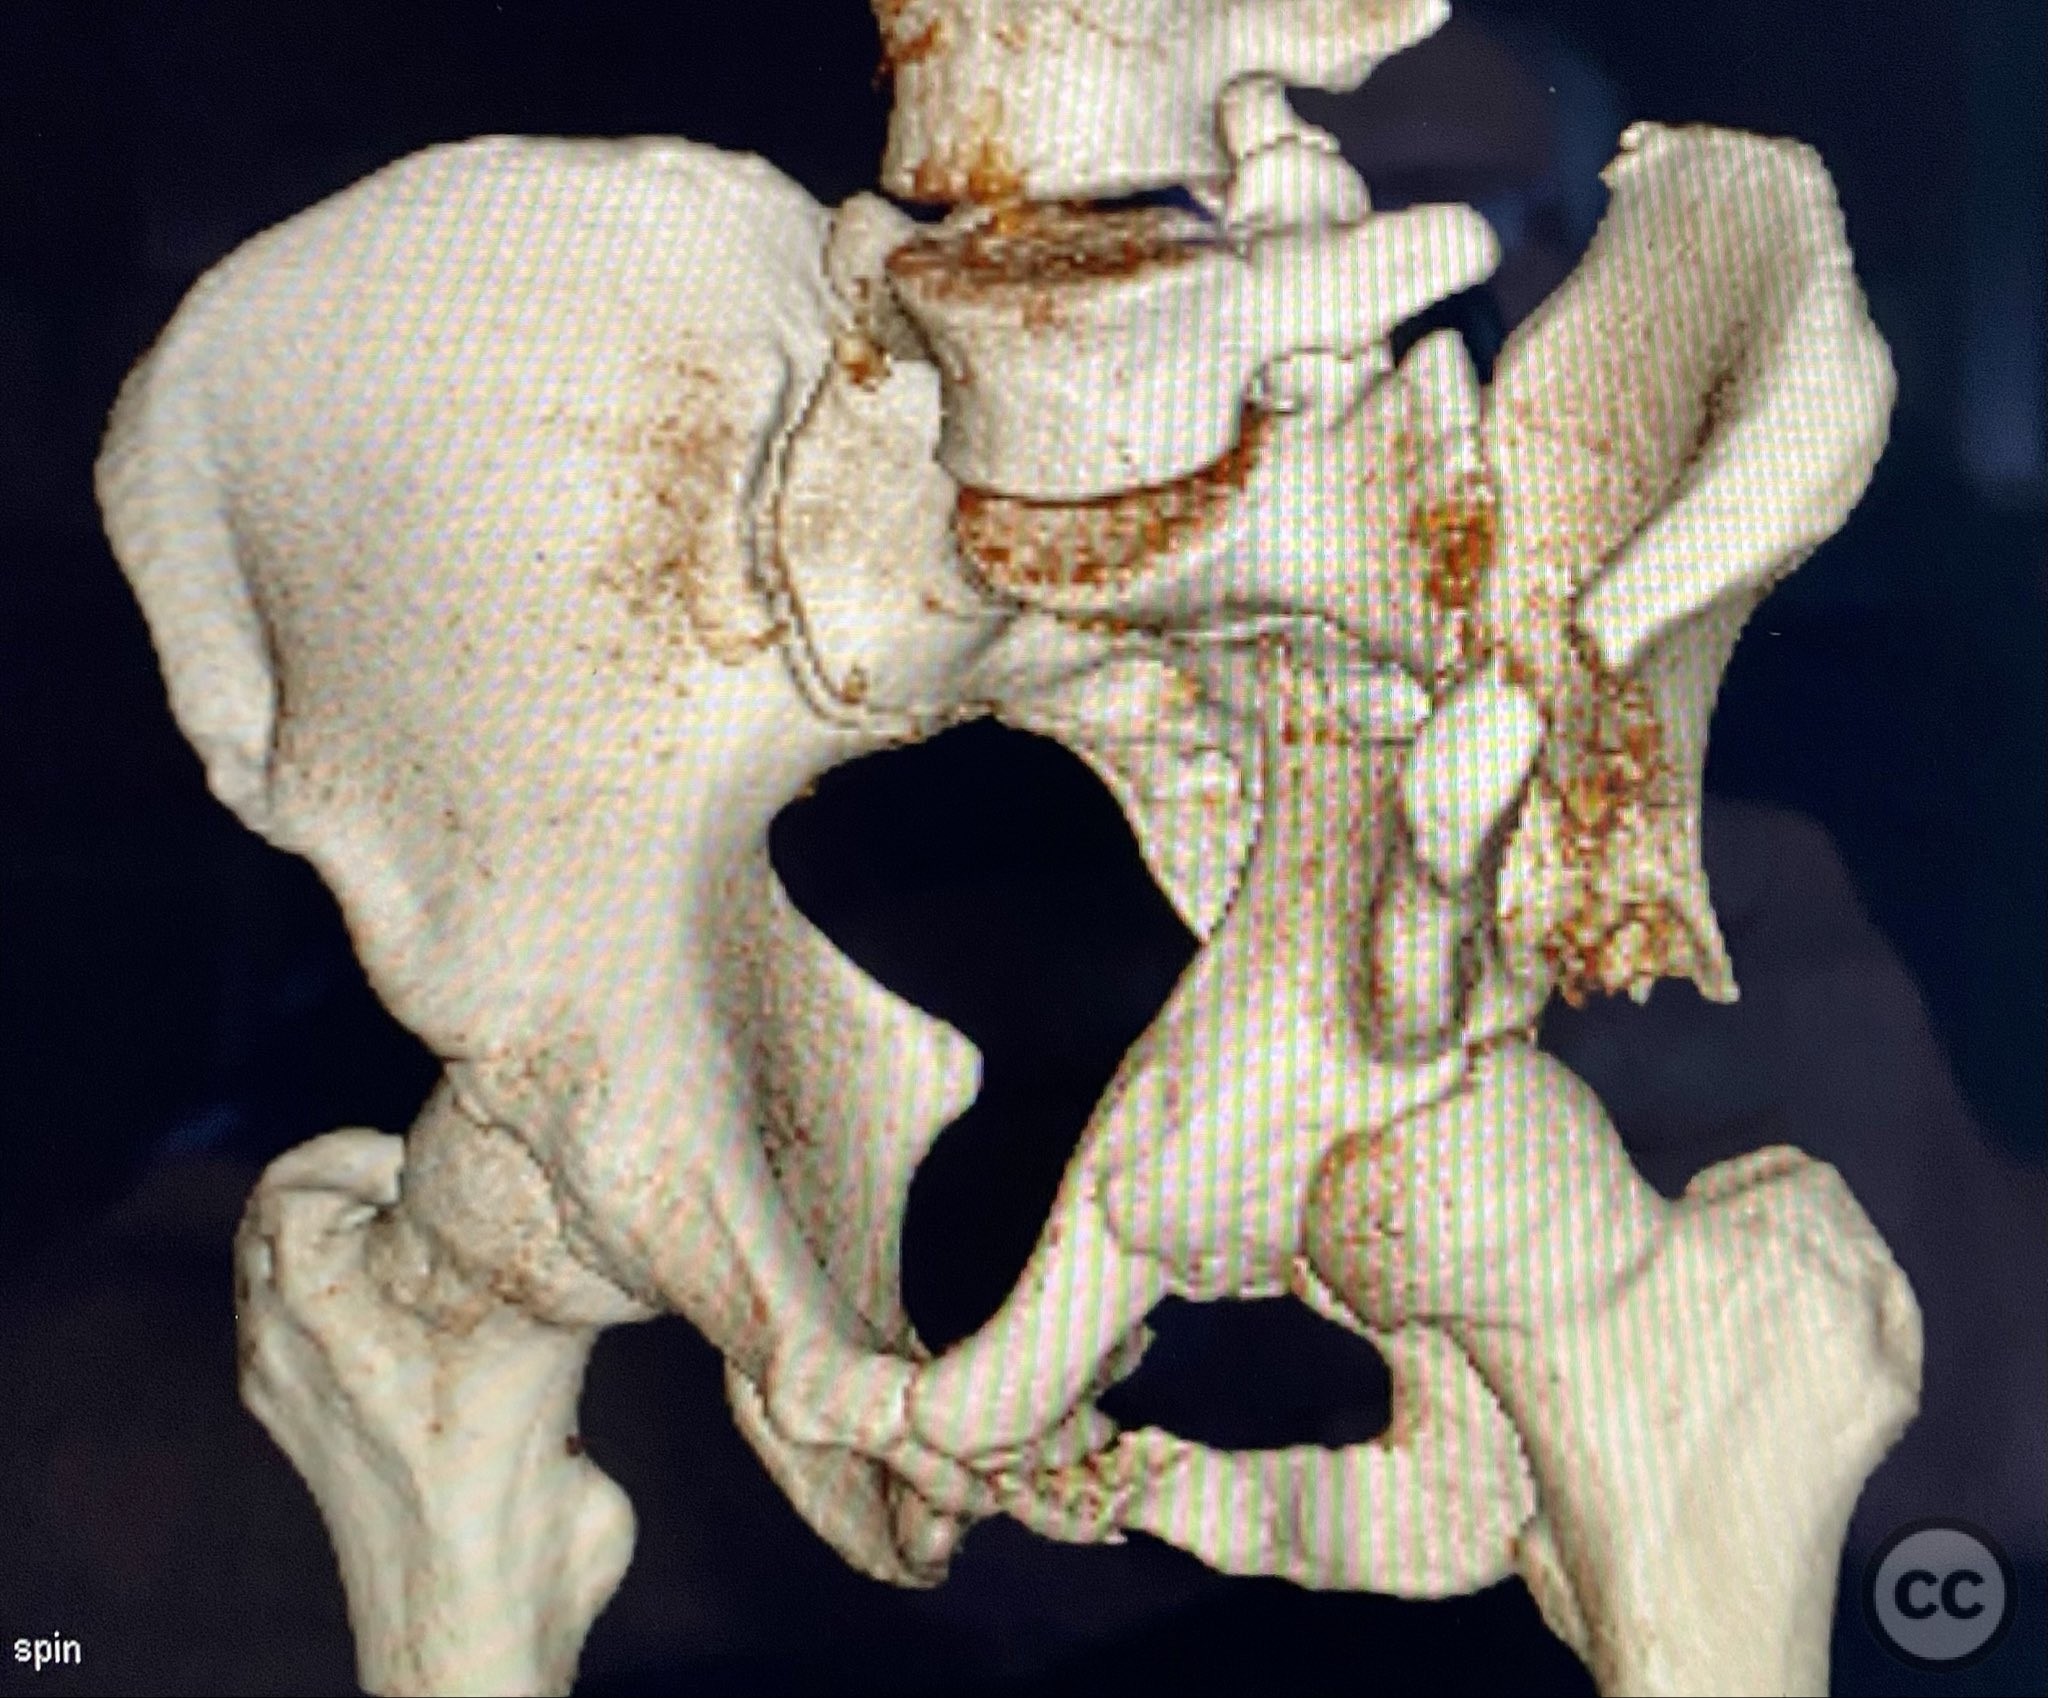

Clinical and radiological findings:  A patient presented with a displaced associated both column acetabular fracture, characterized radiographically by the presence of the "spur sign" on the anteroposterior (AP) pelvis film, indicating the caudal aspect of the intact ilium exposed by medial displacement of the articular fragments. The spur was more clearly visualized on the obturator oblique rendered image. Axial computed tomography (CT) images demonstrated the intact ilium, medially displaced anterior column (AC) and posterior column (PC) fragments, and provided detailed visualization of surrounding soft tissues, including vascular structures enhanced by contrast. Multiplanar CT reconstructions (axial, sagittal, coronal) and 3D renderings were utilized for comprehensive fracture and soft tissue assessment. The patient’s overall clinical condition was a significant factor in surgical planning.

Planning remarks:  The preoperative plan involved open reduction and internal fixation (ORIF) of the anterior column via the ilioinguinal approach, utilizing two separate windows for exposure and reduction. Given the patient’s clinical status, a staged approach was selected: initial AC reduction and fixation, with planned subsequent percutaneous reduction and fixation of the PC. Implant positioning during the first operation was planned to avoid obstructing subsequent percutaneous PC fixation.